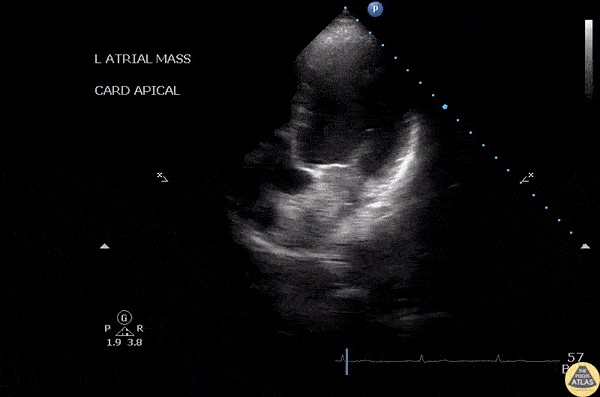

Apical 4 chamber view of a patient with dyspnea of exertion revealed a left atrial myxoma. Image courtesy of Robert Jones DO, FACEP @RJonesSonoEM Director, Emergency Ultrasound; MetroHealth Medical Center; Professor, Case Western Reserve Medical School, Cleveland, OH View his original post here